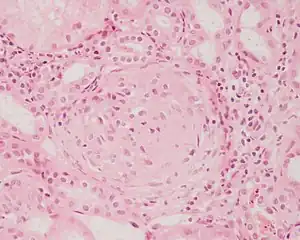

Histologicamente, são classificadas em várias entidades, uma vez que a glomerulonefrite pode ter diversas apresentações clínicas. Raramente essas patologias evoluem para insuficiência renal terminal em questão de semanas, geralmente sua evolução é mais lenta e pode demorar meses ou até anos. Quando ocorre piora da função renal em poucas semanas, elas são classificadas como glomerulonefrites rapidamente progressivas, independentemente do tipo histológico.

Considerando todos os glomérulos presentes no tecido renal temos os seguintes termos:

- Lesão difusa: 50% ou mais dos os glomérulos do rim estão acometidos.

- Lesão focal: Menos de 50 % dos glomérulos estão acometidos.

Considerando apenas um glomérulo temos:

- Lesão segmentar: ocorre quando parte ou segmento do glomérulo está acometido.

- Lesão global: todo o tufo capilar de um glomérulo está lesado.